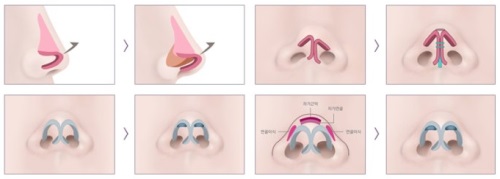

三、擅长各类复杂鼻修复手术

李海兵医生擅长处理各类复杂的鼻修复情况。

比如,一些患者在初次隆鼻手术后出现了假体移位、感染等问题,导致鼻部形态不佳甚至影响正常功能。

李医生凭借优质的技术,能够精密地取出假体,处理感染部位,并重新塑造出理想的鼻部形态。

对于多次鼻修复的患者,他们的鼻部组织已经受到多次损伤,修复难度极大。

但李医生凭借对鼻部解剖结构的深入了解和丰富的临床经验,能够制定个性化的修复方案,更大程度地改善鼻部问题。